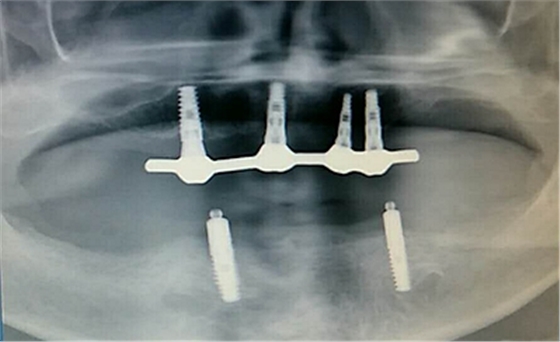

毛國斌種植病例——群討論分享